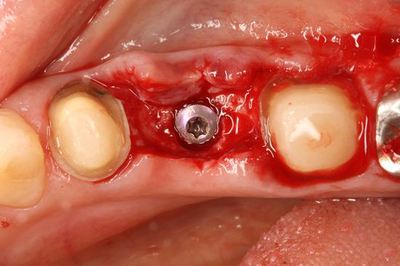

インプラントの埋入を終えました。

インプラントフィクスチャーの上部です。

カバースクリュー高さ0.5mmで封鎖します。

カバースクリューで封鎖しました。